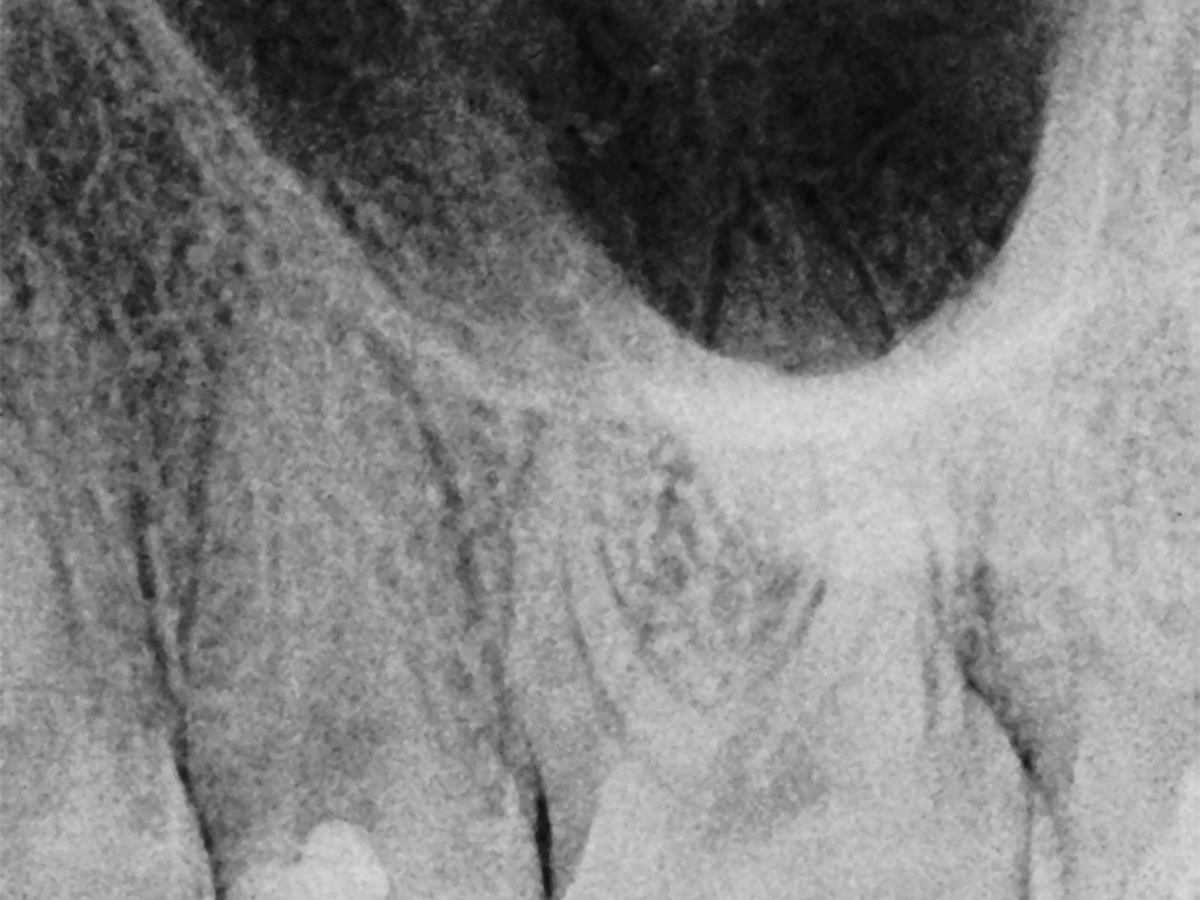

Abbildung 14

Recall: Aufnahme des Zahnes 25 fünf Monate nach Kappung.